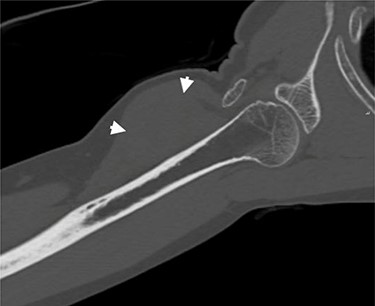

Coronal CT of the right arm. Short arrows indicate the tumoral mass.

A successive non-contrast-enhanced computed tomography (CT) of the right upper arm confirmed the radiographic findings; a well-circumscribed isodense mass beneath the deltoid muscle without embedded calcifications or ossification (Fig. 4), the possibility of myositis ossificans was thereby excluded and a soft tissue tumor of fibroblastic origin became more likely.

Radiographs can identify soft-tissue nonspecific masses. When present, calcifications, osseous erosion of invasion can be detected [13]. CT imaging portrays the mass with a homogeneous structure, similar to skeletal musculature. The description of intramuscular desmoplastic fibroblastoma can show moderate heterogeneity with peripheral attenuation subtly greater than that of skeletal muscle [13].